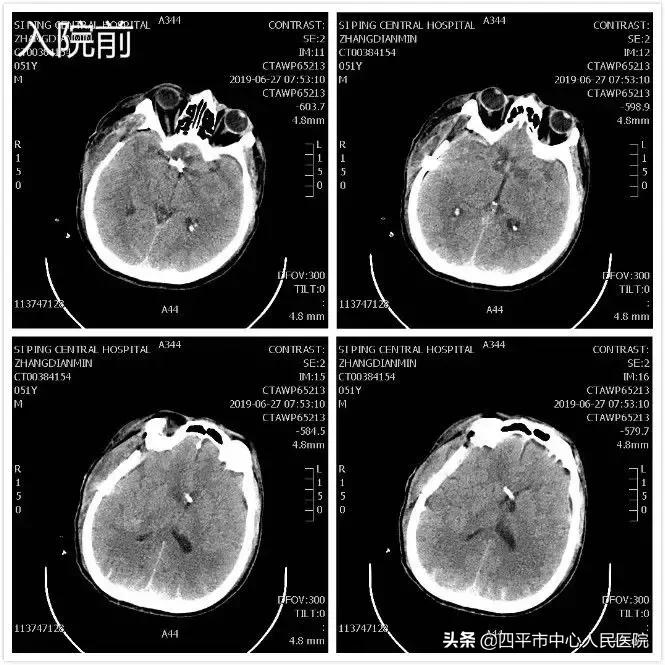

Case4 大量蛛网膜下腔出血颅内动脉瘤开颅探查术

患者张XX,于入院前2小时突发神志不清,伴恶心呕吐,呕吐物为胃内容物,四肢不动,伴尿*禁失**,无抽搐。由家属送至梨树县医院,行头CT检查提示脑出血,为求进一步治疗转送至我院,我院神经内科给予复查头CT提示大量蛛网膜下腔出血,首先颅内动脉瘤破裂所致,由于患者到我院时深度昏迷状态,呼吸微弱,HUNT-HESS分级5级,不适合行头部CTA检查及介入栓塞治疗,家属强烈要求手术治疗,请麻醉科行气管插管后入手术室,李晓东主任带领马龙急诊全麻下经左侧扩大翼点入路行右侧脑室外引流术及颅内动脉瘤探查术,术中探查患者左侧后交通动脉巨大瘤,临时阻断颈内动脉后给予确切夹闭,术中动脉瘤没再次有破裂出血。术后第1天,患者呈浅昏迷状态,刺痛可定位,四肢可自主活动。复查头部CT满意,查头部CTA见左侧后交通动脉瘤夹闭确切。但患者于术后第3天,出现迟发性脑内血肿,考虑到预后不好,家属放弃治疗出院,临出院时对我科李晓东主任及马龙医生的积极救治表示感谢。